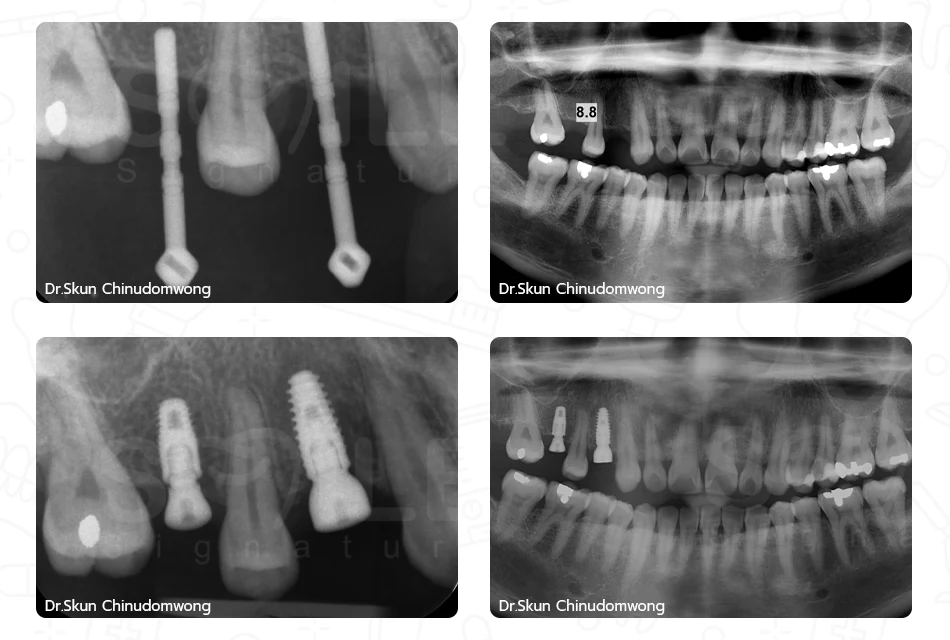

การรักษาด้วยการการปลูกกระดูก (Block Graft)

การผ่าตัดยกไซนัส (Sinus Augmentation)